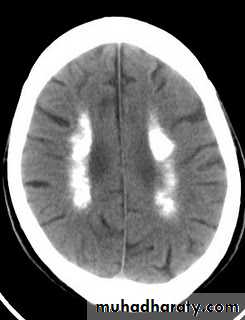

Because of associated hyperphosphataemia, patients with hypoparathyroidism may develop calcification of the basal ganglia, grand mal seizure, psychosis and cataract.Management of hypocalcaemia